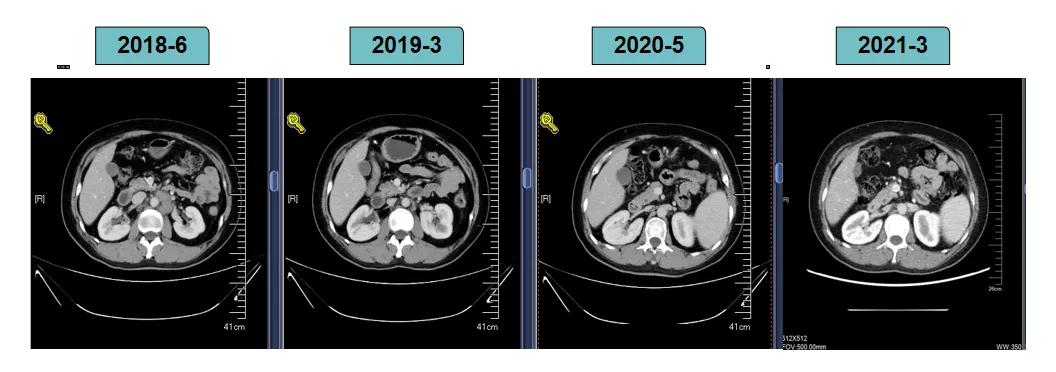

2018-7-17成功入组ELAINA临床研究(试验方案编号:BO29919),IWRS分配随机号3210。于2018-7-17开始接受T-DM1 3.6mg/kg(252mg)治疗,并间断对其进行疗效评估。现阶段患者PFS达近40个月。

影像学评估-纵膈淋巴结:

影像学评估-肝脏:

影像学评估-腹膜后淋巴结: